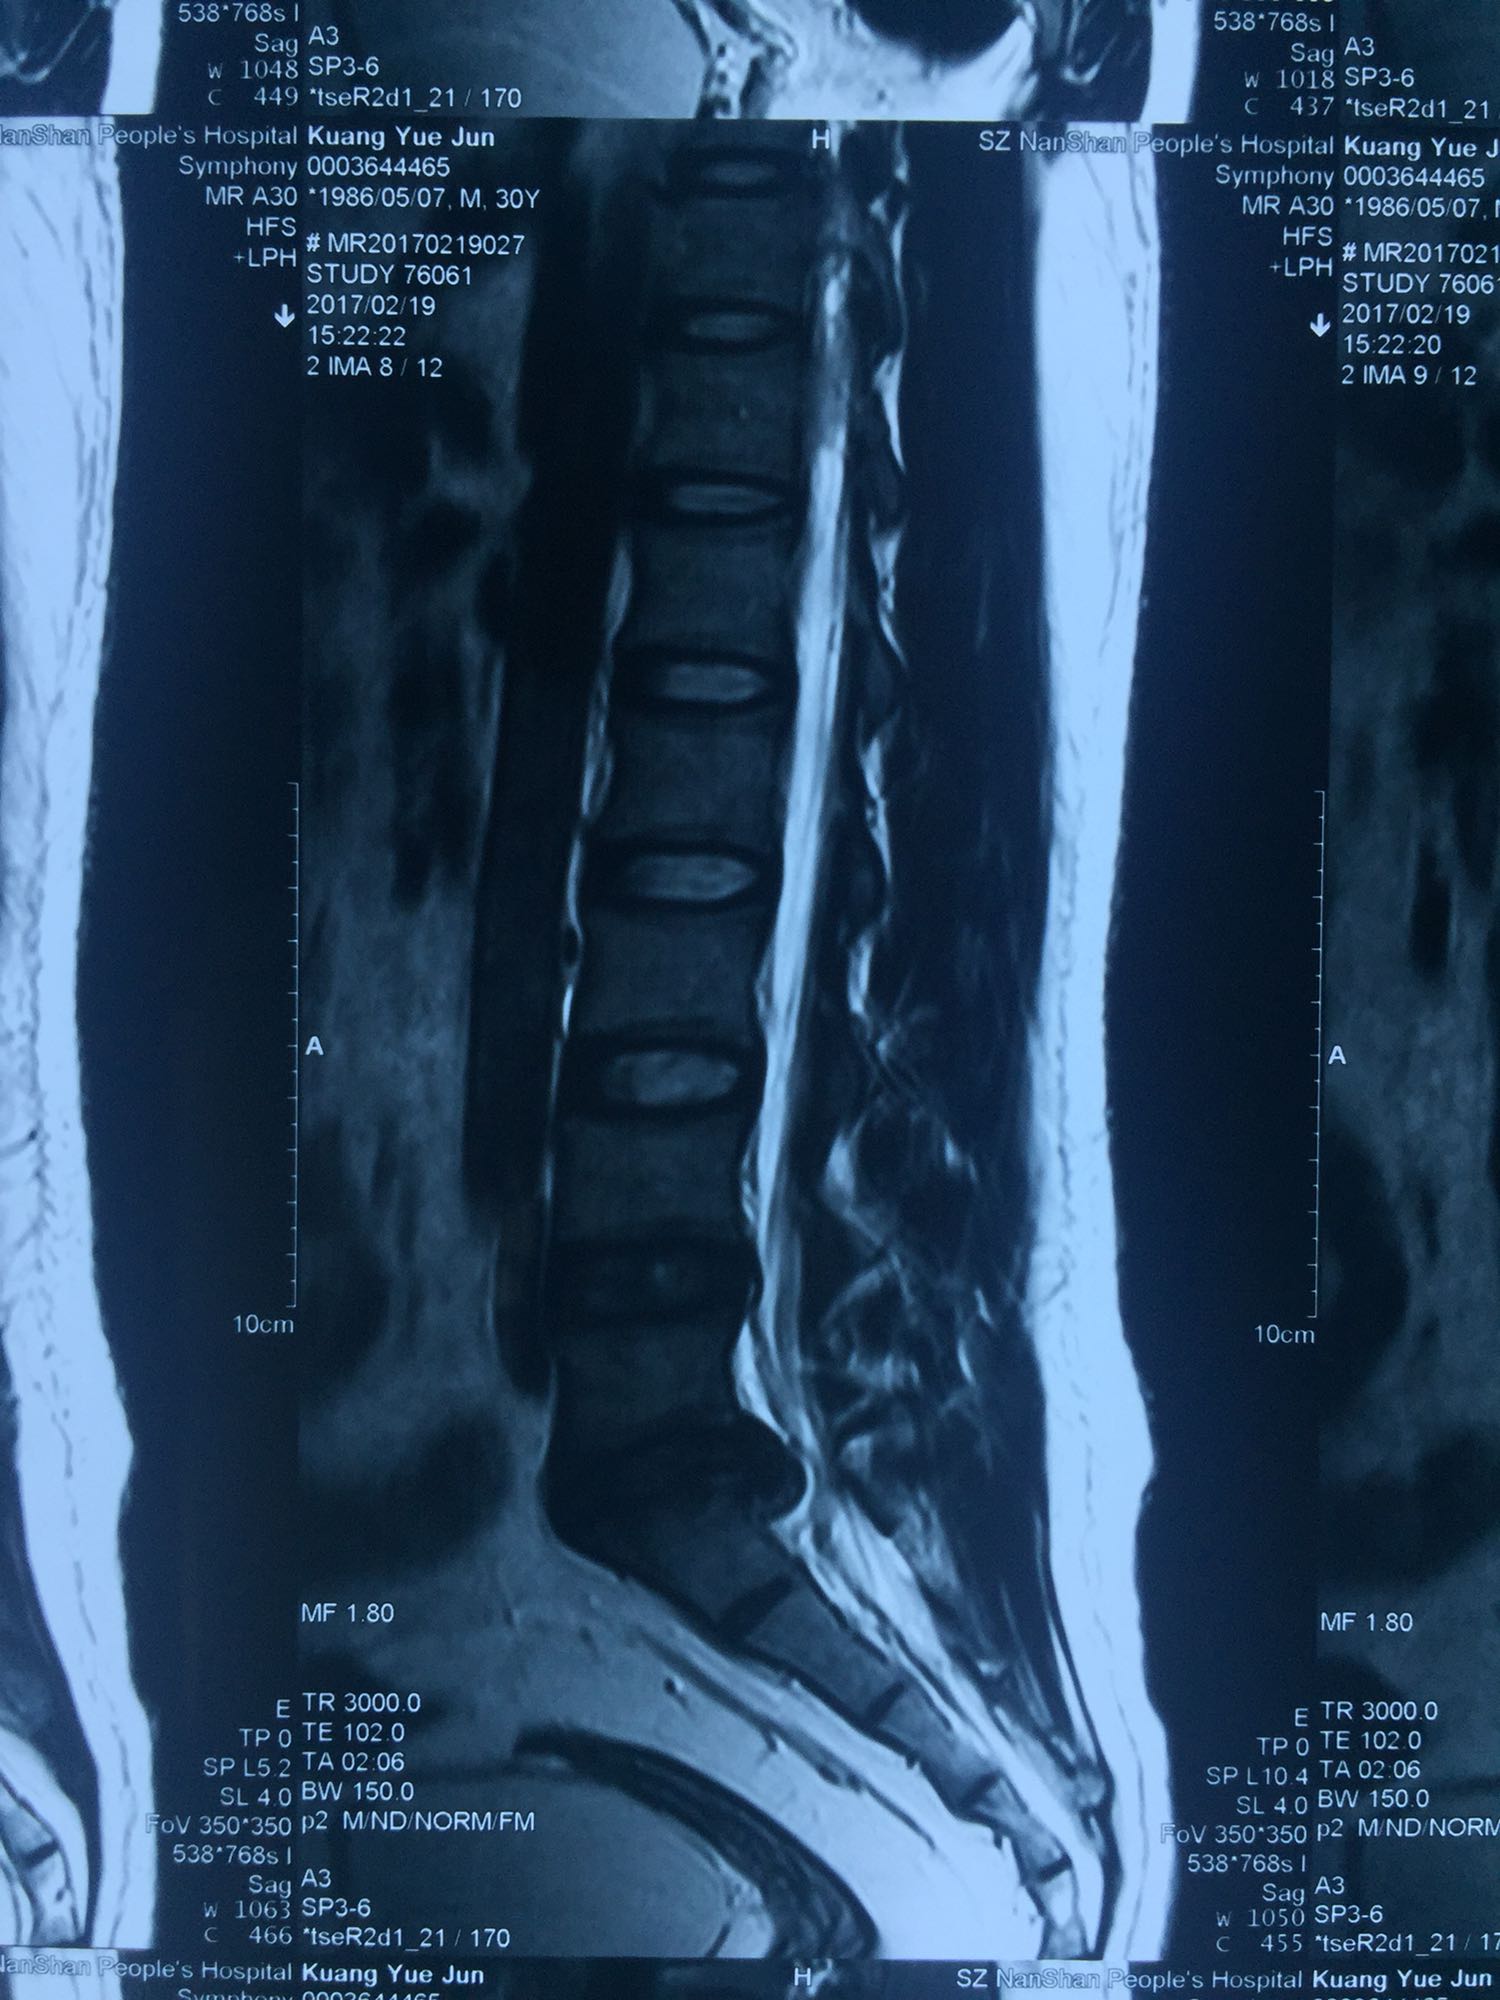

椎间孔镜下腰5骶1椎板间隙入路髓核摘除术

腰椎间盘脱出

腰骶部肌紧张,腰5骶1棘间及左侧椎旁有压痛及放散痛,左侧坐骨神经出孔处有压痛及放散痛,左侧足背外侧及足底部皮肤感觉麻木,左侧直腿抬高试验阳性(30度)。

诊断:腰5骶1椎间盘突出症 治疗方案:椎间孔镜下经椎板间入路髓核摘除术